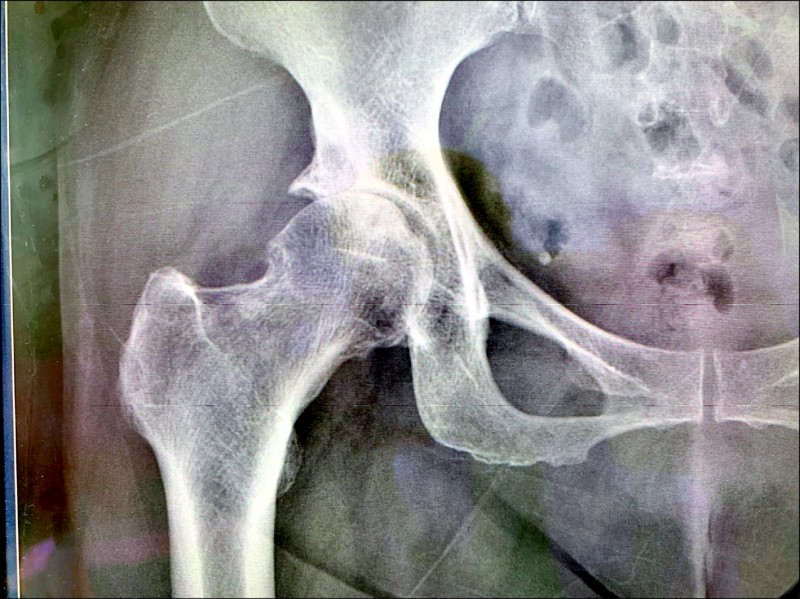

郴州骨科医院在线科普 引起髋关节疼痛的常见疾病有哪些 活动

大腿疼痛跛行全髖關節置換助恢復生活品質 永越健康管理中心

阿嬤髖關節退化難走路醫師一招治療重拾走路樂趣 骨科 復健 該看哪科 元氣網

髋关节疼痛 僵硬 活动受限 髋关节骨性关节炎可以这样应对 于运动

屁股大腿痛 髖關節炎 剖析髖關節位置 原因及退化要吃什麼 Esdlife健康網購